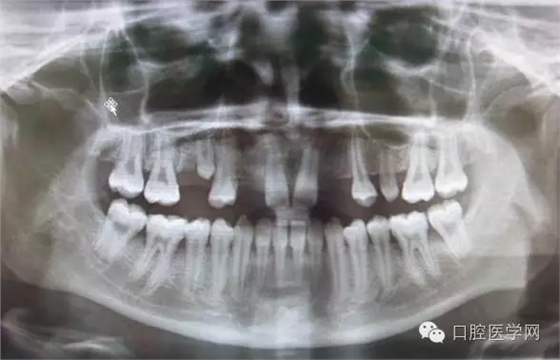

4.阻生牙

最常見(jiàn)于下頜第三磨牙

X線表現(xiàn):確定阻生牙的位置;確定阻生方向;牙根數(shù)目和形態(tài);阻生牙有無(wú)齲齒和根尖情況;與第二磨牙的關(guān)系;與下頜管的距離和磨牙后間隙的大小。